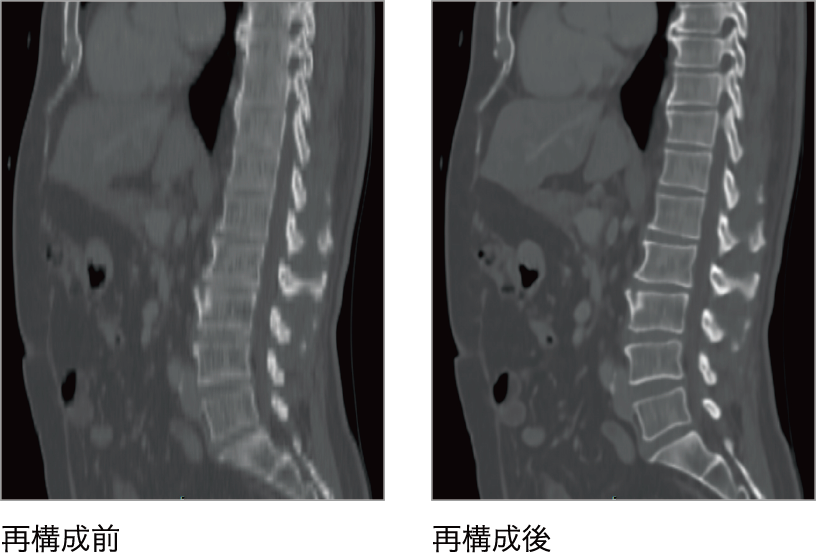

SAI viewer上でVR、MIPに再構成し、任意の角度でボリュームを観察。